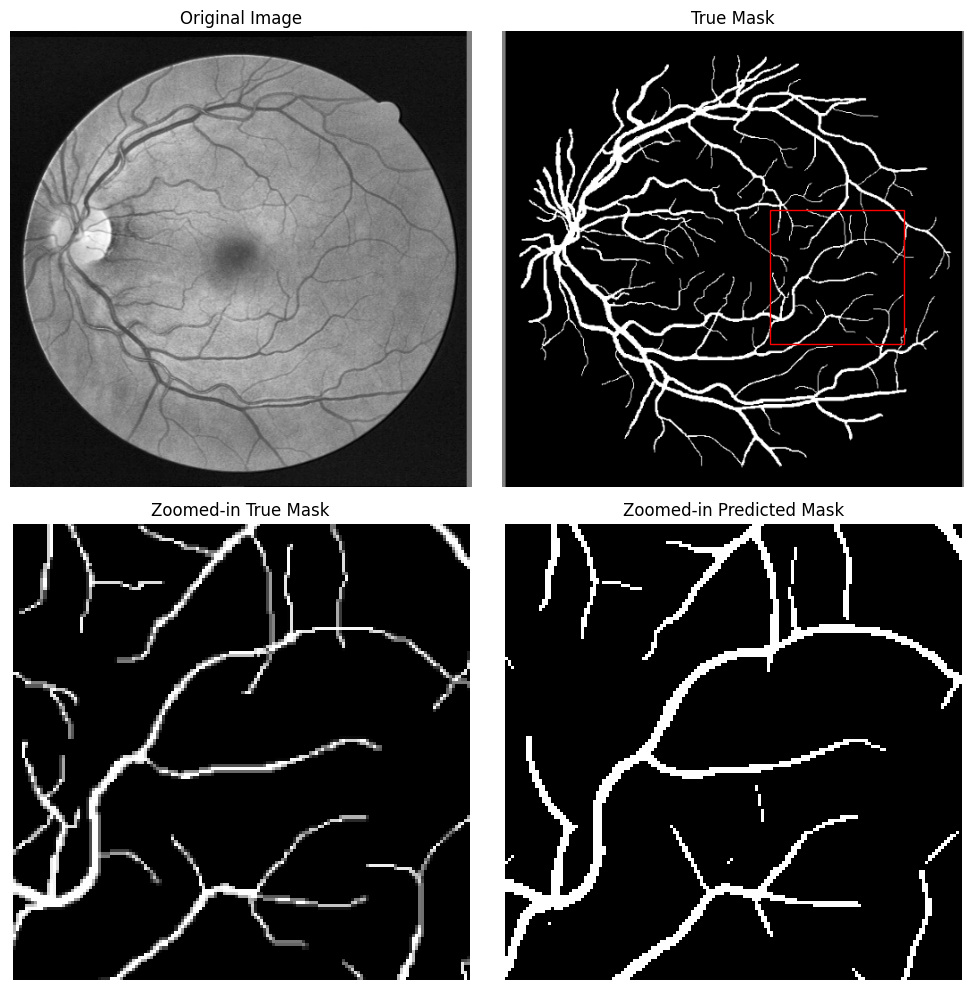

In this subsection, we analyze the predicted masks generated by our U-Net model for retinal vessel segmentation. A representative example of a predicted mask alongside the corresponding ground truth mask is presented in Figure 9. This visual comparison highlights the model’s ability to segment retinal vessels with notable accuracy while also revealing areas where the model’s performance could be improved.

a= Note: Test images are modified via CLAHE as part of predicted mask generation.

The predicted mask (Fig. 9c) demonstrates that the U-Net model is generally effective at identifying and segmenting the main blood vessels within the retinal image. The larger and more prominent vessels are clearly delineated, which is crucial for many clinical applications, such as diagnosing and monitoring retinal diseases.

However, despite the overall strong performance, the model exhibits limitations in detecting finer and more minute blood vessels. These smaller vessels are often essential for comprehensive retinal health assessments, yet they pose a challenge due to their subtle and less distinct appearance compared to larger vessels. As observed in Figure 10, several thin and intricate vessels are either partially detected or entirely missed. Additionally, predicted vessels sometimes appear thicker than their corresponding true mask counterparts.

We believe that the resolution (512x512) of the input images and the scale of the vessels significantly impacted the model’s ability to detect fine details. The U-Net architecture, while powerful, would require higher resolution inputs or additional fine-tuning to capture the minutiae of retinal vasculature. However, this was not possible in this study due to the amount of compute resources required for the processing of high resolution imagery.